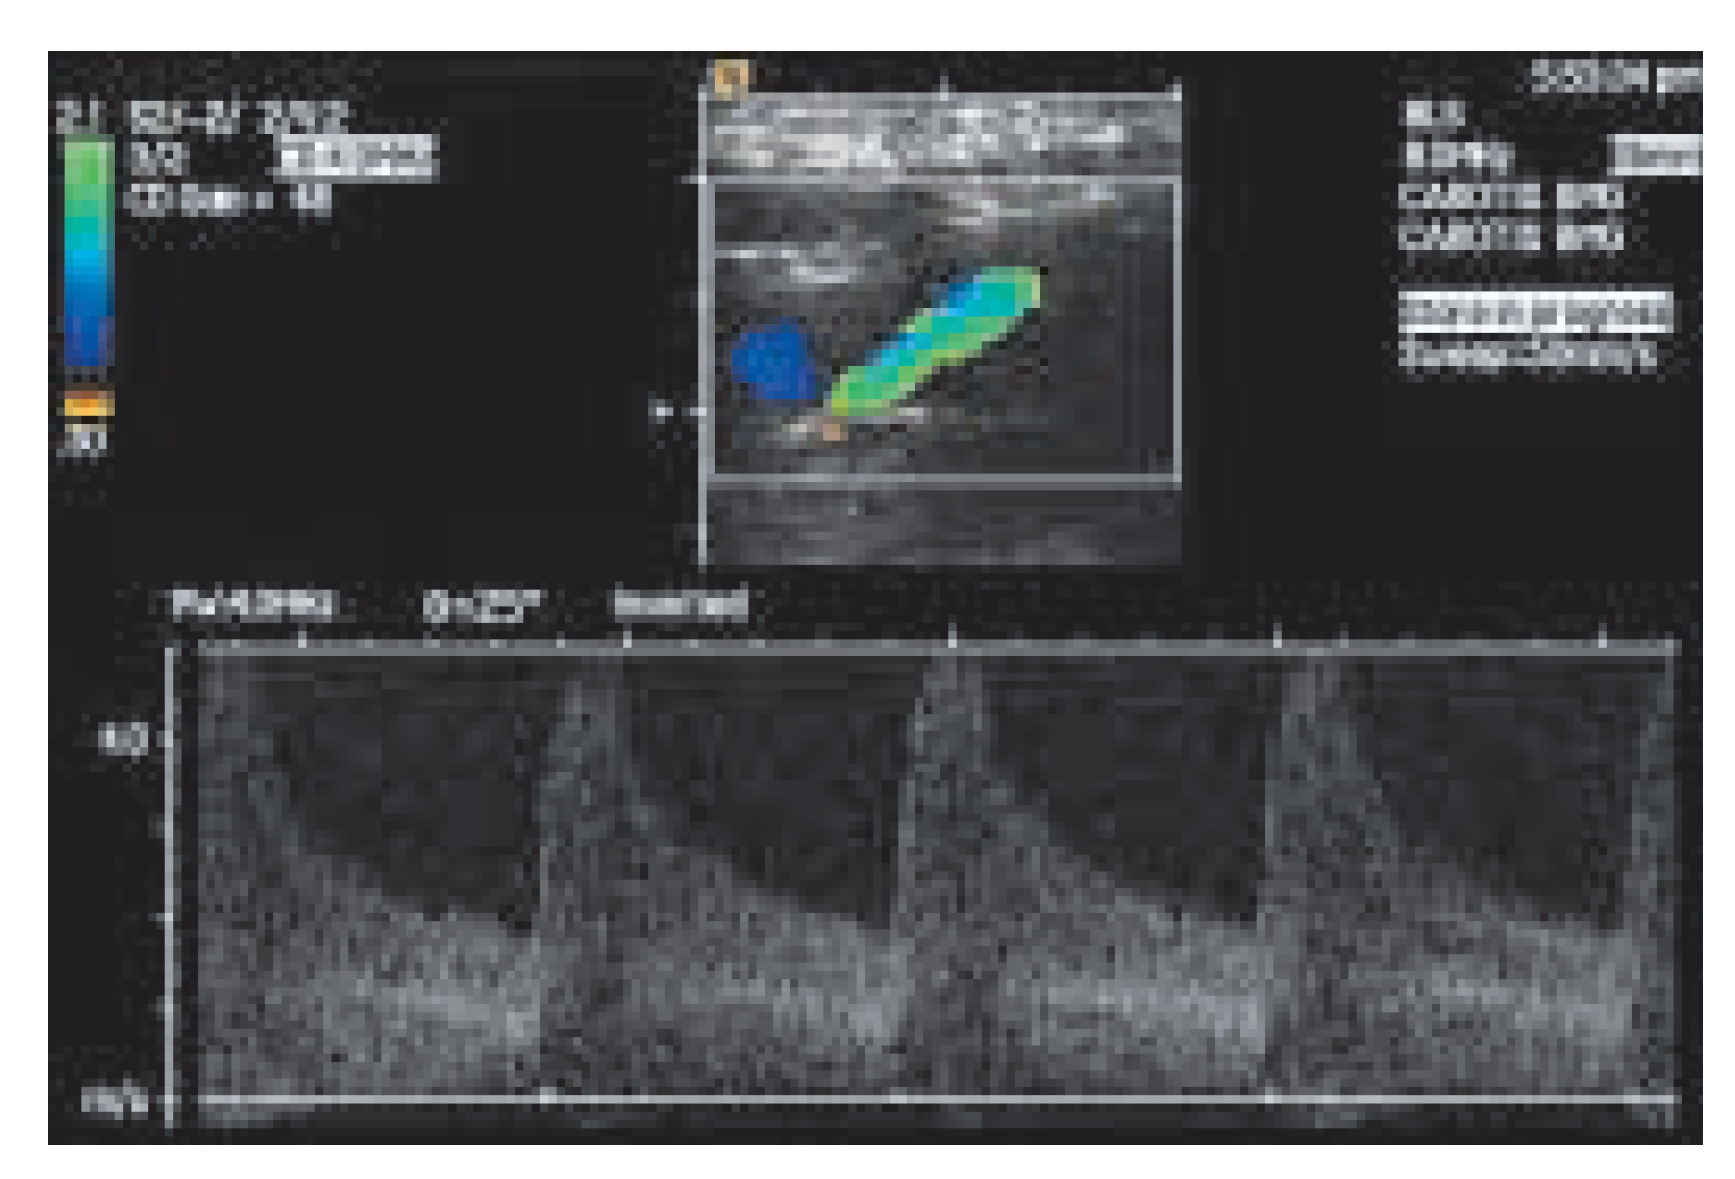

Ultrasonographische Verfahren